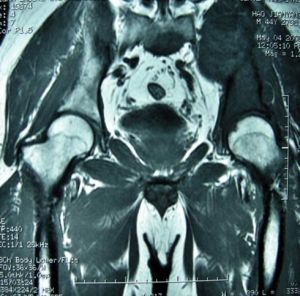

MRI

非常有助於判斷腫瘤的範圍和對輔助治療的反應。由於MRI可以顯示腫瘤三維六個方向上的範圍,因此可以用於計畫各個方向上的切除邊界,即MRI可以顯示腫瘤在遠、近、內、外、前、後各個方向上的範圍,並以此為依據計畫各方向上相應的切除邊界,發現最困難的切除部位,完善術前準備。

由於骨盆腫瘤切除重建手術複雜,因此在術前應仔細分析患者的影像資料,明確腫瘤的骨內和骨外軟組織腫塊的範圍。